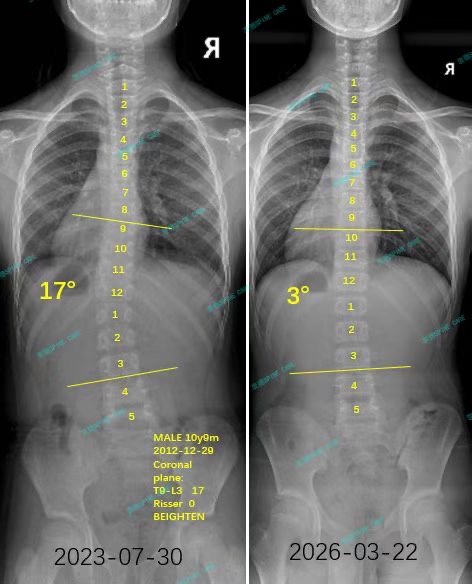

来自家长对衷德的评价(小俊妈妈)

衷德脊柱,我们只关注侧弯保守治疗~

Zhongde Spine, bending no breaking ~